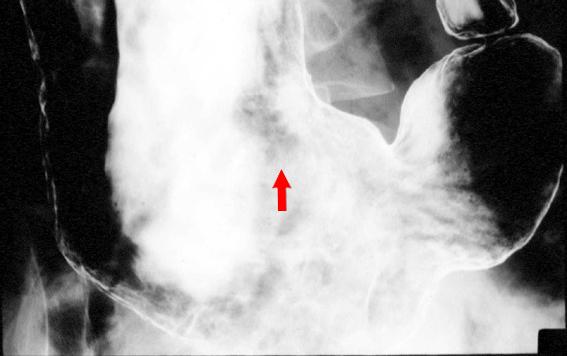

A case of gastric malignant lymphoma showing spontaneous regression without anti cancer drug therapy.

Malignant Lymphoma/MLP type

Location

Stomach/Body

Technique, Method

X-ray

Size

20 - 24